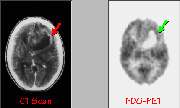

Click on image above to view full-size image.

The preferred treatment of brain tumors is surgical removal. FDG-PET scans are useful for evaluating the efficacy of surgical procedures. In the above case, PET confirmed that the contrast enhancement observed with CT prior to surgery (A, green arrow) represented a region of hypermetabolism (A, red arrow). Such a hypermetabolic region suggests the presence of a high-grade tumor. Postoperatively, the primary indication for FDG-PET studies is to identify foci of tumor recurrence. Contrast enhancing lesions on CT scans (e.g., B, green arrow) may represent tumor recurrence or radiation necrosis. The lack of a corresponding hypermetabolic region in the FDG-PET image suggests that the contrast enhancement observed in the CT scan (B) is due to post-surgical trauma, and that no residual tumor was present at that time. However, several months later (C), a hypermetabolic rim reappears in the FDG-PET image (C, red arrow), indicating a recurrence of the tumor.